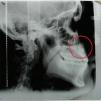

Examen radiográficoEn la radiografía panorámica se observan dos dientes supernumerarios entre los incisivos laterales y primeros premolares superiores, y la impactación de los caninos maxilares permanentes sobre las raíces de los incisivos centrales superiores. Se observa la reabsorción de un tercio de la raíz del incisivo central superior derecho y de los tercios apicales del incisivo lateral del mismo lado y del incisivo central y lateral del lado opuesto. En la radiografía lateral se observa la retención de los caninos permanentes por vestibular (Figuras 3 y 4).

Los análisis cefalométricos revelaron una clase II esqueletal por biprotrusión, crecimiento horizontal, biotipo braquifacial y protrusión y proclinación dental superior e inferior (Figuras 5 a 7).